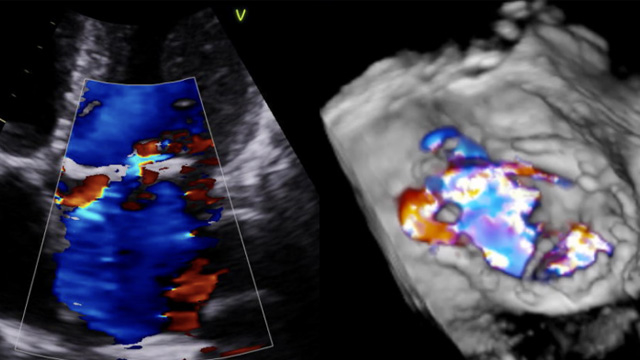

Watch this session to discover the best cases and abstracts unveiled at PCR Tokyo Valves 2023, covering topics such as transcatheter aortic valve implantation impact, cerebral protection efficacy, and post-TAVI aortic regurgitation quantification.